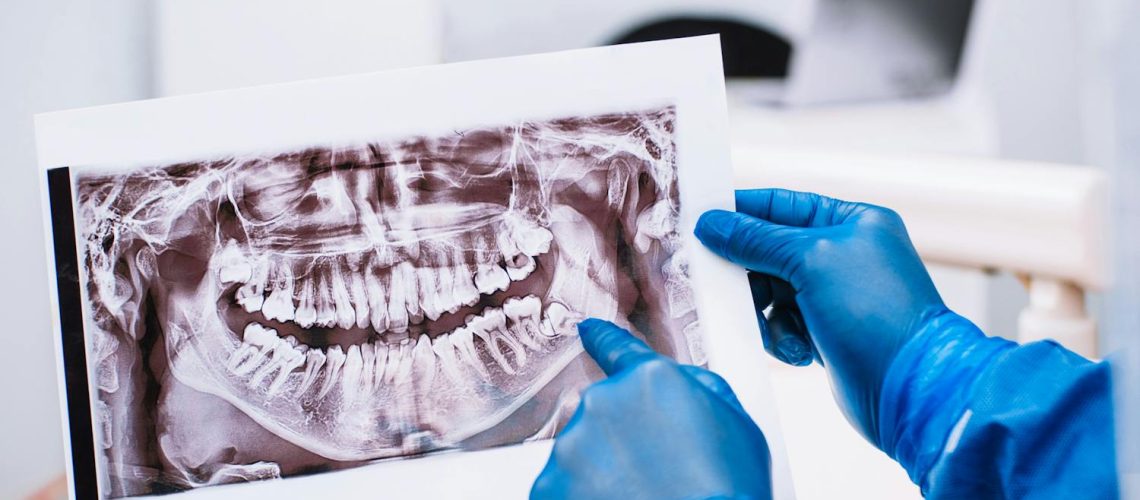

Manque de place, poussée dentaire douloureuse, péri-coronarite : il est parfois nécessaire d’extraire les dents de sagesse. Quelles sont les suites de l’intervention ? Que manger après ? Le point avec le Dr Jérémy Amzalag, chirurgien-dentiste et coauteur de l’ouvrage Prendre soin de ses dents pour les nuls ainsi que de l’encyclopédie médico-dentaire en ligne Capitaldents.com

Manque de place, poussée dentaire douloureuse, péri-coronarite : il est parfois nécessaire d’extraire les dents de sagesse. Quelles sont les suites de l’intervention ? Que manger après ? Le point avec le Dr Jérémy Amzalag, chirurgien-dentiste et coauteur de l’ouvrage Prendre soin de ses dents pour les nuls ainsi que de l’encyclopédie médico-dentaire en ligne Capitaldents.com Read More Santé